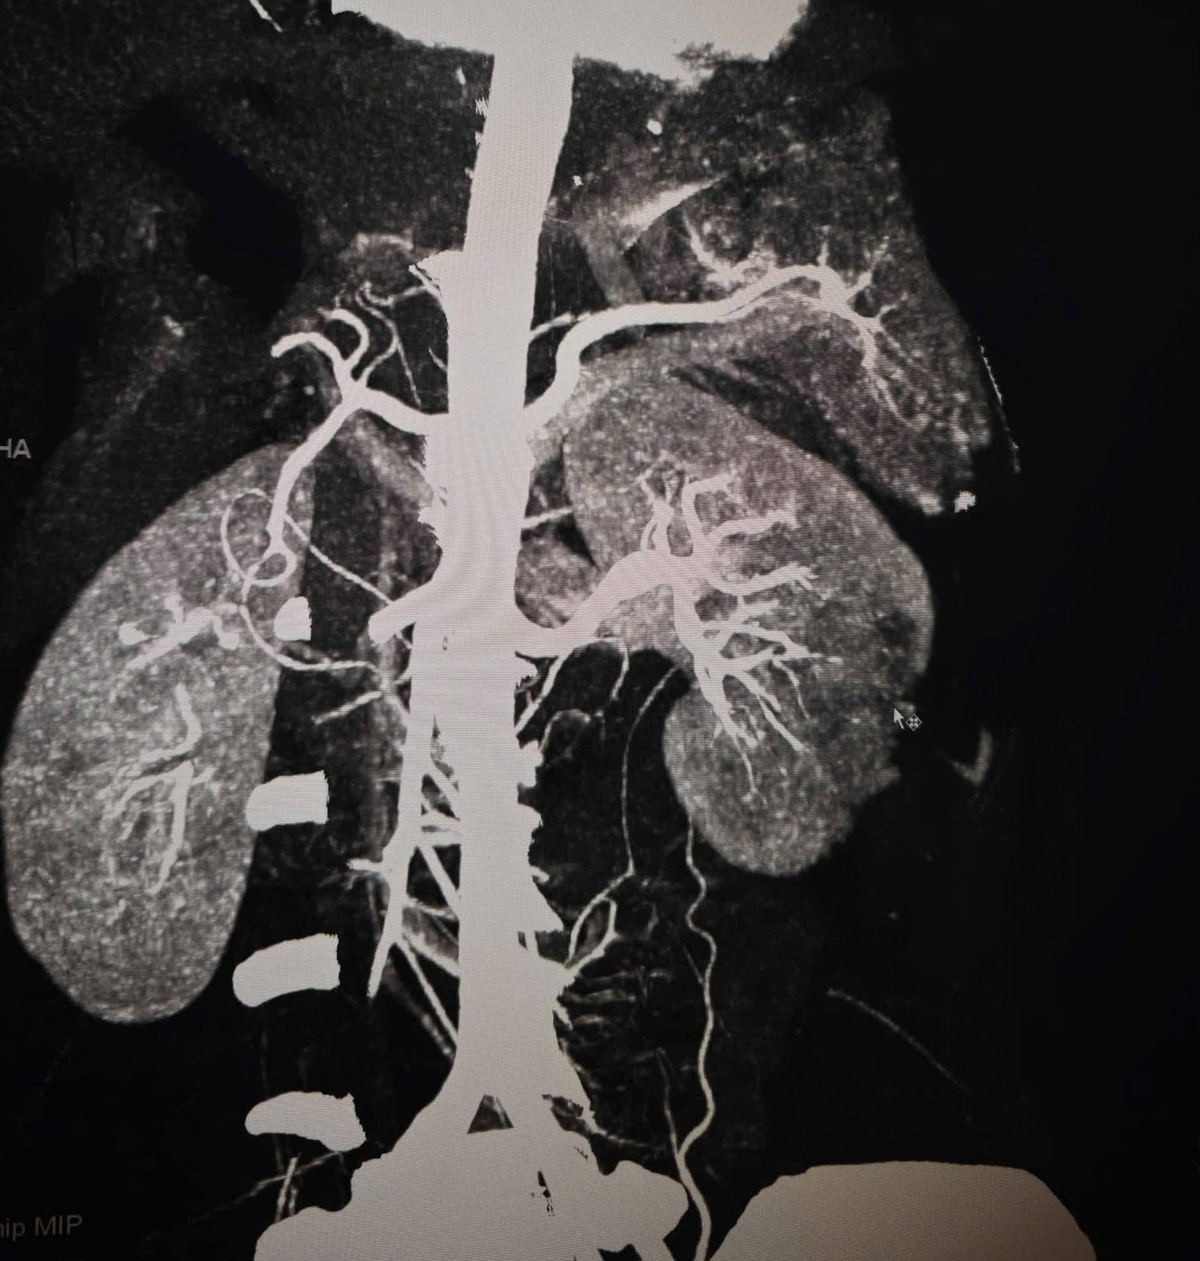

Hình ảnh thận vỡ trên phim chụp - Ảnh BVCC

Kết quả chụp CT cho thấy tổn thương rất nặng: vỡ lách phức tạp, vỡ thận độ IV có giả phình mạch và chảy máu hoạt động, kèm tràn máu ổ bụng. Tình trạng này có thể gây sốc mất máu bất cứ lúc nào nếu không xử trí khẩn cấp.

Hình ảnh thận và lách vỡ trên phim chụp - Ảnh BVCC